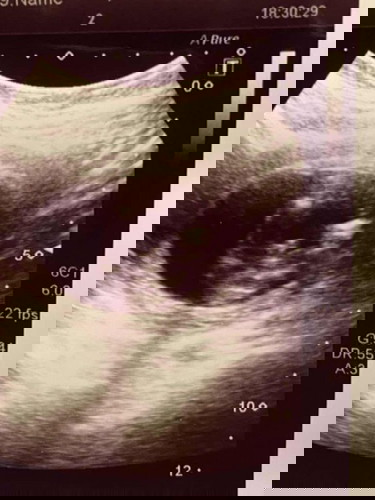

ใครเคยเป็นไหมคับ? แปลกไหมครับ ผมมีความสุขทุกครั้งที่ได้มาโรงพยาบาล อยากจะซาวทุกวันด้วยซ้ำไป 🥰 วันนี้ครบ 4 เดือนแล้ว พอยิ่งรู้ว่าลูกเป็นเพศ ช หรือ ญ ยิ่งรู้สึกดีขึ้นไปอีก. รู้สึกดีในที่นี้ ไม่ได้หมายความว่า ผมมีเป้าหมายที่อยากได้ผู้ชายหรือผู้หญิง แต่ผมก็จะได้มีเป้าหมายไปอีกขั้น ว่าเป็นลุกผู้ชาย เขาจะเป็นยังไงน้า ....... ❤️❤️❤️